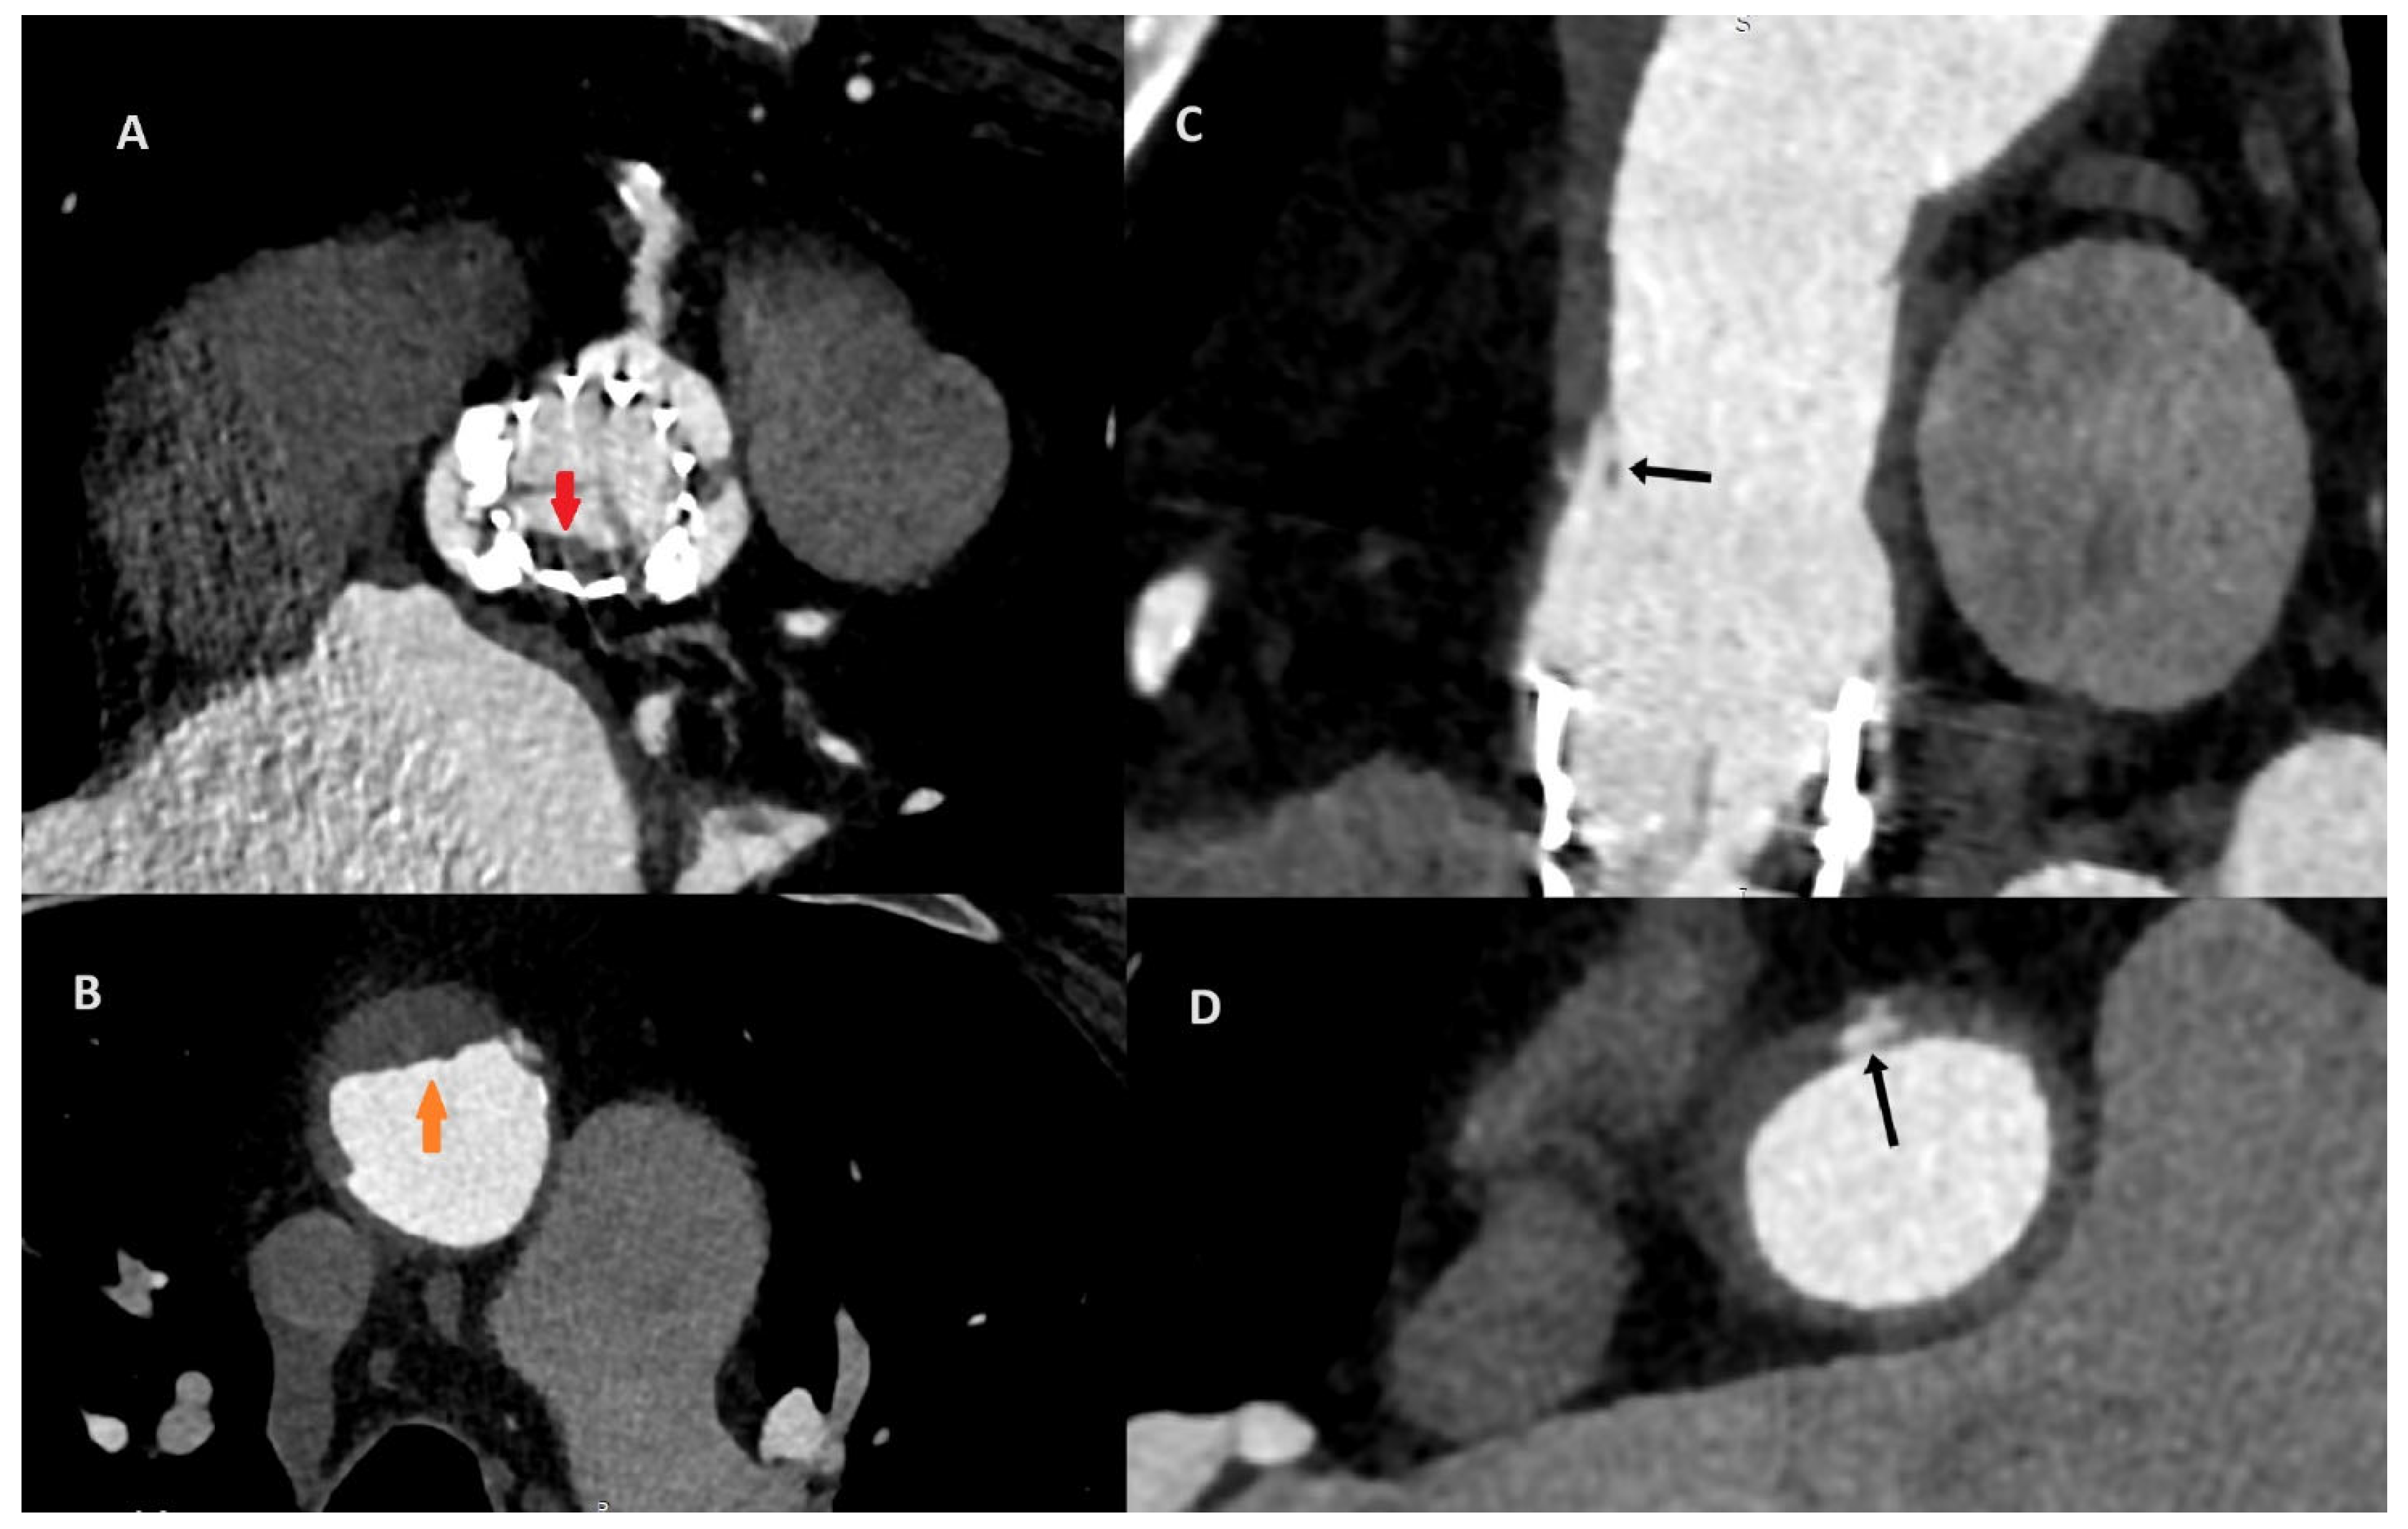

Figure 2. After the consultation with the cardiac radiologist, the third ECG-gated cardiac CT was performed on the eighth day after the initial CT to access both the aorta and coronary arteries. To increase the quality of the image, an additional beta-blocker and nitroglycerin were administered before examination. The CT revealed aortic valve prosthesis thrombosis (A; red arrow) and a reduction in aortic thrombosis (B; orange arrow). The previous thrombus site was localized to originate within the ascending aorta graft, which was covered by soft tissue that resembled an ulcer. The probable dissection of the neointima along the prosthesis was the suspected cause of the initial aortic thrombosis (C,D; black arrow).